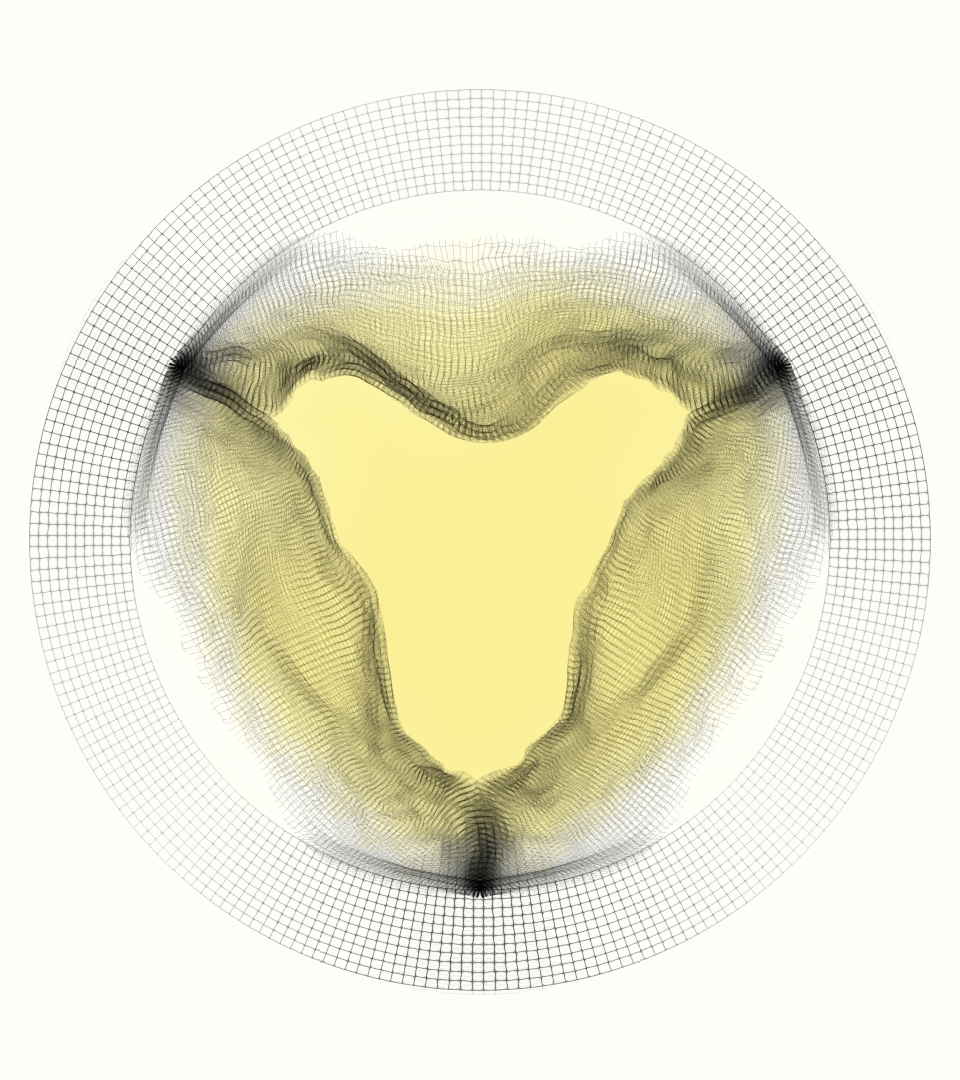

Slice views of the (axial) component of fluid velocity in the axial plane, orthogonal to the flow direction, show that the simulation replicated the development of the jet over the cardiac cycle. At each phase, the simulation matched the forward speed of the core of the jet and the locations of reverse flow back towards the valve annulus. While there are some differences in the shape of the jet at certain phases and locations, the simulation clearly produced the general dynamics of the cardiac cycle that are seen in the experiment.

At = 0, the axial slice directly at the valve annulus shown in columns 1 and 2 in Figure 6, there was excellent agreement between the simulation and experiment over the cardiac cycle in the speed and shape of the jet through the valve. In both cases, the axial velocity increased as the flow accelerated during systole and the valve leaflets opened, then decreased during diastole with slight negative velocity before the valve leaflets were fully closed. The forward flow through the valve annulus did not form a full circle, but rather developed a triangular shape with a point of the triangle forming along the interior curve of the vessel, at the bottom of the axial slices. At = 0, the points of this triangular jet shape aligned with the commissures of the valve. This shape persisted during peak systole and was well-matched by the simulation.

The axial slice = 0.625 cm, shown in columns 3 and 4 in Figure 6, cut through the support scaffolding of the valve and the leaflets when they are open. In the experimental data, the shape of the jet changed as it moved downstream. A triangular shape occurred, but the points were then aligned with the middle of each open leaflet as opposed to the commissures. Those points were also more rounded than they were at = 0. The peak velocity of the jet was faster at = 0.625 cm than at = 0, as the flow accelerated through the open valve leaflets. The simulation produced these features at = 0.625 cm. The triangular shape of the jet shifted similarly, and its speed increased compared to the upstream slice. As the flow decelerated into diastole, the jet shape remained roughly triangular but diminished in intensity before disappearing after valve closure.

The jet continued to develop at = 1.25 cm, an axial slice immediately downstream of the valve scaffolding and open leaflets, shown in columns 5 and 6 in Figure 6. In the experimental data, the points of the triangular jet shape extended further towards the vessel wall. In addition, regions of reversed flow developed in the locations downstream of the commissures, resulting in curved sides to the shape of the jet. Each tip of the jet was unique, due to variations in the individual leaflets in the physical bioprosthetic valve. These variations are apparent in the velocity fields, possibly because the jet edges are similar enough cycle to cycle that irregularities are still being captured even with phase averaging. Further discussion of these features can be found in Schiavone et al. [39], which showed that the jet tip shapes occurred in different pulmonary anatomies, demonstrating that they were likely due to inherent properties of each leaflet. The leaflets in the mathematical model of the valve are identical, so these nuances in leaflet variation could not be replicated. The simulation did capture some of the extension of the tips of the jet, as they were closer to vessel wall at slice = 1.25 cm than = 0.625 cm. The curves in the triangular sides of the jet were also present in the simulation, though they were less pronounced than the experimental data. At both = 0.625 cm and = 1.25 cm, the jet shape in the simulation was smoother than the jet in experiment. It is possible that the free edges of the leaflets in the mathematical model are not fully replicating the behavior of the physical leaflets of the bioprosthetic valve, in particular the amplitude or frequency of leaflet flutter, leading to the variations seen in the jet shape at = 1.25 cm downstream of the leaflet edges. The simulation, however, does capture the key features of the triangular shape and speed of the jet. Overall, qualitative comparisons demonstrated that the simulation reproduced key features of the flow during systole and diastole.